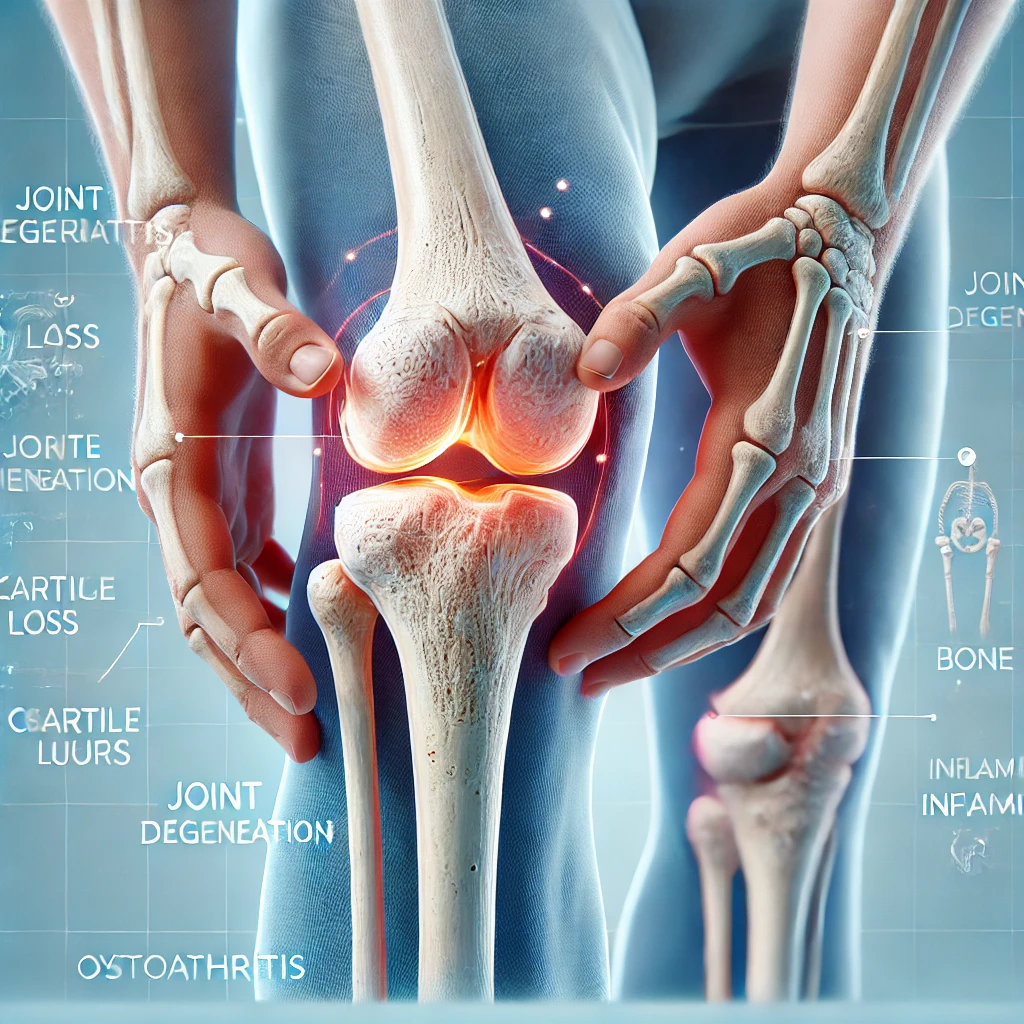

Osteoarthritis

Osteoarthritis (OA) is the most common form of arthritis,

characterized by the gradual degeneration of joint cartilage and the underlying bone.

It primarily affects the weight-bearing joints, such as the knees, hips, lower back, and

hands, leading to pain, stiffness, and limited mobility. OA is considered a

degenerative joint disease (DJD) and is associated with aging and wear and tear of

the joints, although other factors can contribute to its development.